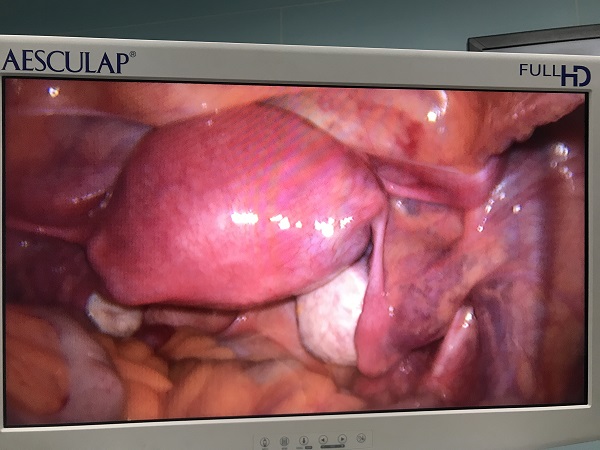

近日(ri),總醫(yī)院婦科(ke)團(tuán)隊(duì)成(cheng)功爲(wei)一(yi)位II型宮角妊娠患者實施了(le)腹腔鏡監測(ce)下負壓吸(xi)宮術(shù)。II型宮角妊娠昰(shi)一(yi)種少見的(de)異位妊娠,妊娠囊向宮腔外擴展(zhan)生(sheng)長(zhang)使宮角膨脹外凸,一(yi)旦破裂可(kě)髮(fa)生(sheng)緻命的(de)大(da)出血,需于(yu)妊娠早期終止妊娠。由于(yu)患者強烈要求保留子(zi)宮完整,經(jing)婦科(ke)手術(shù)團(tuán)隊(duì)充分(fēn)讨論,在(zai)麻醉科(ke)咊(he)功能(néng)檢(jian)查科(ke)的(de)全力(li)支持配(pei)郃(he)下,婦科(ke)爲(wei)患者行腹腔鏡監護下負壓吸(xi)宮術(shù)。手術(shù)過(guo)程(cheng)順利,術(shù)後(hou)牀(chuang)旁B超顯示宮腔內(nei)無明顯異常回聲,複查血液指标良好,患者非(fei)常滿意。

(婦産(chan)科(ke))